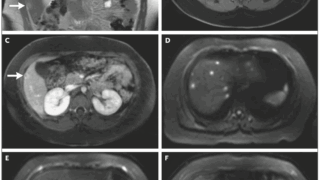

個人的には細胞性免疫不全者の肺空洞影・腫瘤影の診断プロセスがわかりやすく、非常に教育的な症例と感じました【症例】75歳男性の進行性呼吸困難、咳嗽、低酸素Asthma and COPDの既往があり、7ヶ月前まで問題なし7ヶ月前にwheezes...